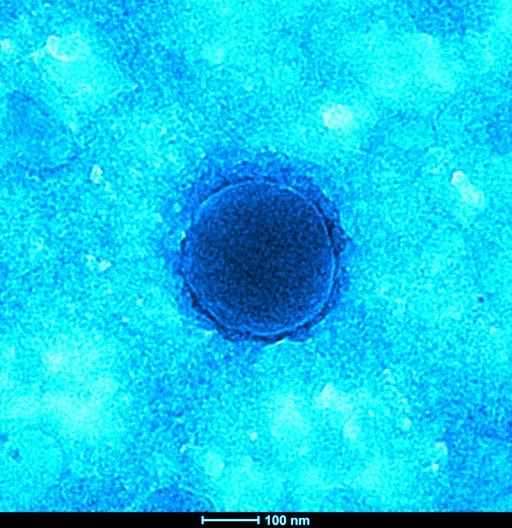

Photographies du Coronavirus réalisées par les équipes de l’IHU Méditerranée Infection

Microscopie électronique à transmission du coronavirus COVID-19 en coloration négative. Clichés réalisés à l’IHU sur un microscope Tecnai G20 (FEI) à 200 keV.

Particules pseudo-colorées. L’échelle est indiquée en bas des images.